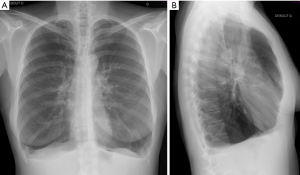

Conventional chest radiography (chest X-ray) has been the backbone of imaging for more than 100 years (13). Although chest X-ray is one of the oldest and least sophisticated imaging examinations, it remains one of the most commonly used methods due to its wide availability, low cost, and fast implementation (14-17). The two most important signs of lung emphysema on X-ray are (I) the barrel shaped thoracic cage with flattening of the hemi-diaphragmatic domes, and (II) hyperlucency of the lung tissue due to overinflation and rarefication of vessels (Figure 2). Auxiliary findings comprise enlargement of the intercostal areas, enlargement of the retrosternal clear space >2.5 cm, narrow configuration of the cardiac silhouette, increased markings pattern, and the presence of bullae (4).

Since, conventional radiography is a projection-based imaging technique, it is often impossible to distinguishing structures of equal density next to each other or overlapping different structures (18). Chest X-ray has only a sensitivity of 40% in identifying emphysema (4), little specificity and high interobserver disagreement. These facts hinder a solid and reproducible quantification of emphysema burden in COPD patients (19).

The main role of X-ray in emphysema is to investigate for concomitant findings that should be evaluated before therapy planning (infection, pleural scarring and pulmonary masses) and plays an essential role in follow-up imaging. Chest X-ray is broadly used for postinterventional evaluation following placement of endobronchial valve, sealant or coil implantation or after LVR and its potential complications such as device displacement or pneumothorax.

For a better representation of the extent and distribution of emphysematous lung changes, as well as for a sensitive recognition of absolute contraindication for LVR procedure, further evaluation with chest CT is advised.